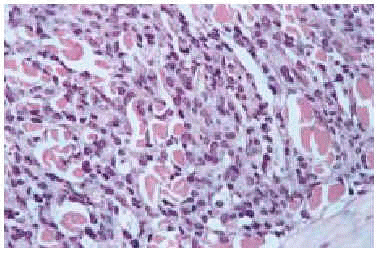

El estudio histológico de las lesiones, tanto de los nódulos como de las maculopápulas, ponía de manifiesto la existencia, bajo una epidermis normal, de un denso infiltrado que ocupaba desde dermis media hasta hipodermis respetando una fina banda superficial (fig. 3). El infiltrado era monomorfo y estaba formado por células de citoplasma escaso y núcleos irregulares con abundantes mitosis (fig. 4). En el estudio inmunohistoquímico se evidenciaba que dichas células pertenecían a la serie monocito-histiocitaria (CD43+, CD68+, CD15+) (fig. 5), con índice proliferativo muy alto (fig. 6).

Fig. 4.--Detalle de las células del infiltrado.